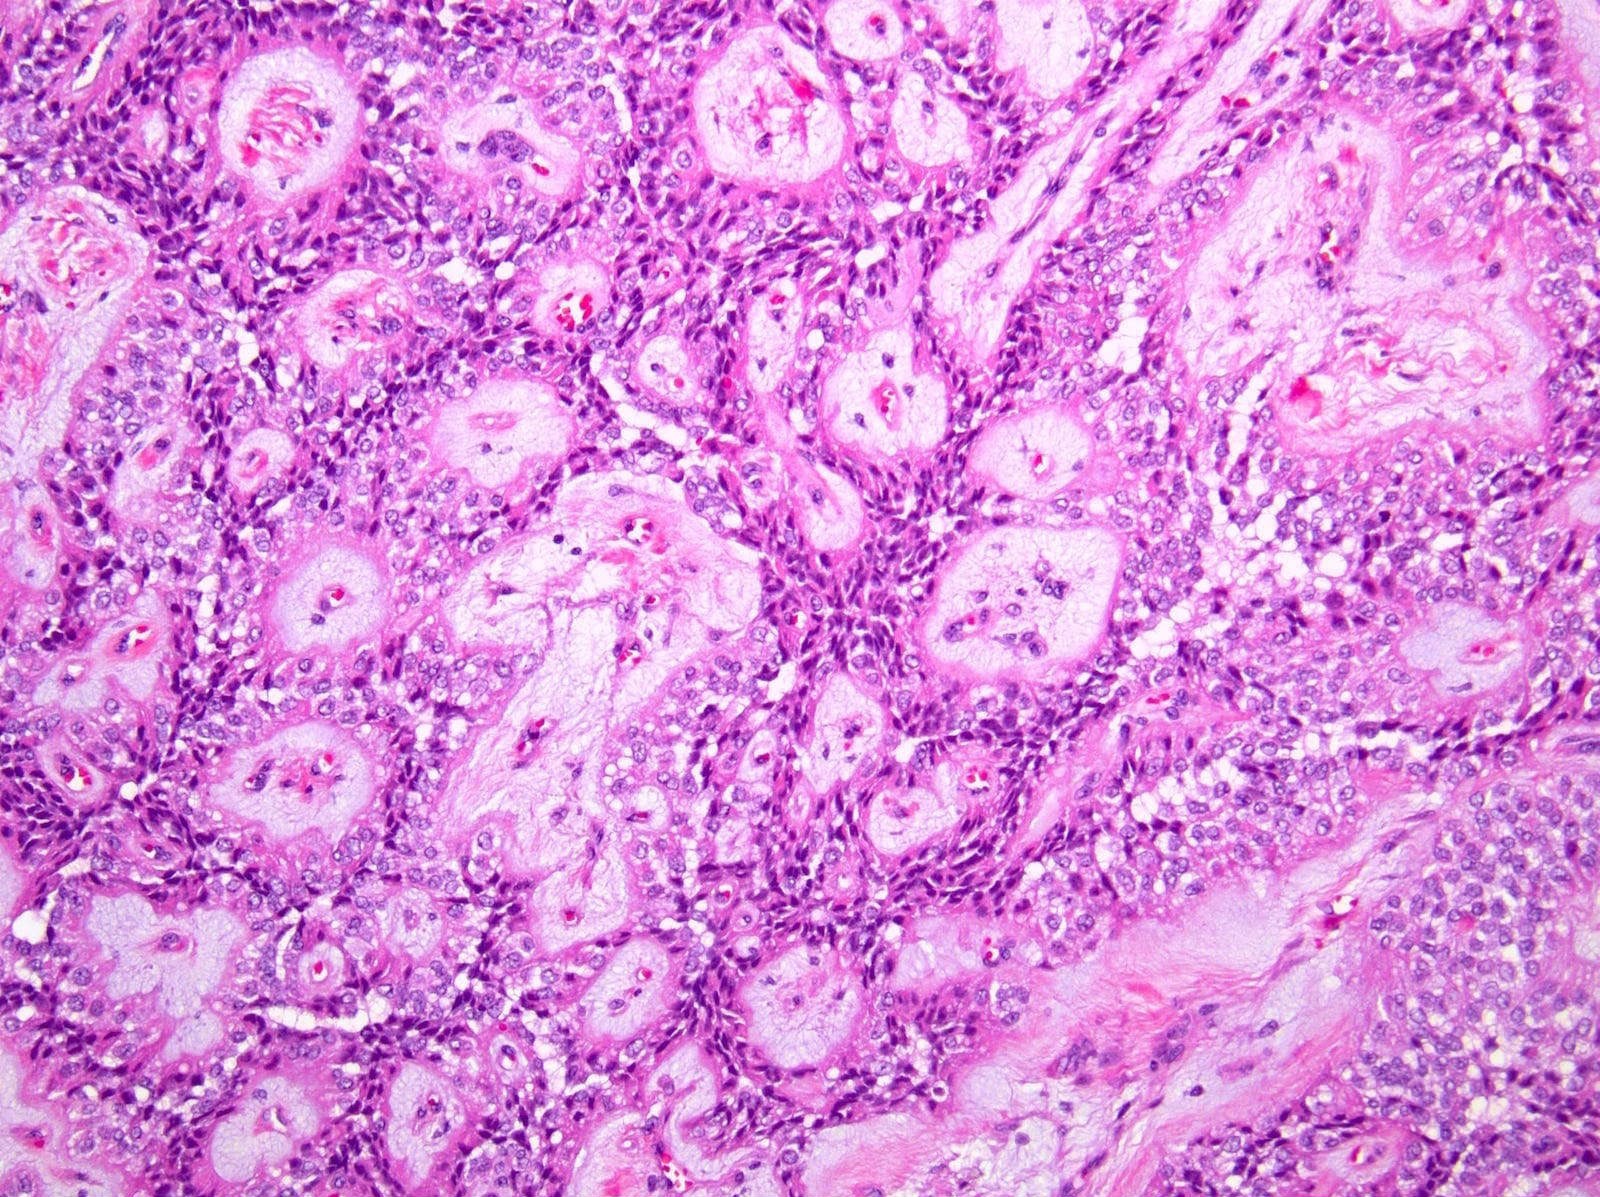

Microscopic (histologic) description

- Tumors are heterogeneous, with variable admixture of solid and pseudopapillary areas

- Solid areas are comprised of uniform cells admixed with capillary sized blood vessels

- Pseudopapillae are formed due to tumor cells getting detached from blood vessels forming fibrovascular stalks or rosette-like structures (Arch Pathol Lab Med 2020;144:829)

- Stroma usually shows various degrees of hyalinization or evidence of degeneration, such as hemorrhage, foamy macrophages, calcification and cholesterol clefts

- Tumor cells usually have a moderate amount of eosinophilic cytoplasm with intracytoplasmic hyaline globules (PAS+ and diastase resistant, positive for alpha-1-antitrypsin) and perinuclear vacuoles (Am J Surg Pathol 2011;35:981)

- Relatively uniform nuclei with finely textured chromatin, inconspicuous nucleoli and characteristic longitudinal grooves

- Variants include clear cell, oncocytic and pleomorphic

- Rare mitotic figures

- Although grossly well circumscribed, microscopic finding of infiltration to the surrounding pancreatic tissue is not uncommon

- Rare cases of highly aggressive behavior; histological features in those cases included diffuse growth pattern, extensive necrosis, significant nuclear atypia, high mitotic count (35 - 70/50 high power fields) or sarcomatoid features (Am J Surg Pathol 2005;29:512)

Microscopic (histologic) images

Contributed by Monika Vyas, M.D., Omid Savari, M.D. and Raul S. Gonzalez, M.D.